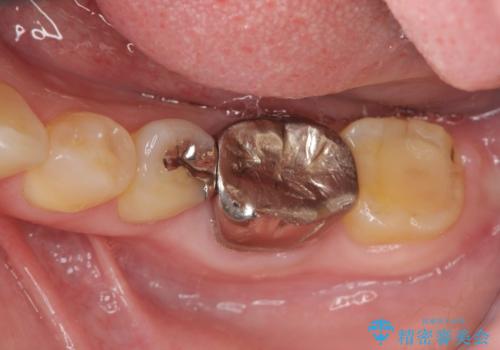

- 銀歯の部分で噛むと痛い、痛みが増している、と治療を希望され来院されました。

- 14.3万円(仮歯・ファイバーコア・ジルコニアクラウン)費用は治療当時の料金となります